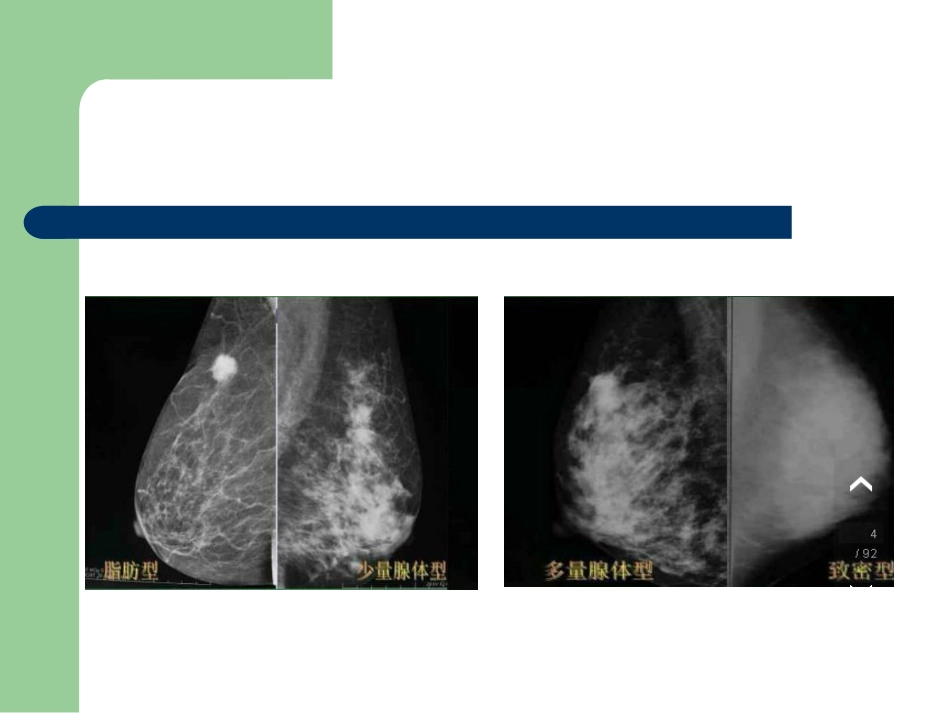

1992年,美国放射学院(AmericanCollegeofRadiology)出版了指导性的文件:乳腺影像报告数据系统(BreastImaging–ReportingAndDataSystem,BI-RADS),其后经3次修订,至2003年不仅指导乳腺X线诊断(第4版),而且,也增加了超声和MRI诊断。对乳腺作为一个整体器官的所有影像学正常与异常情况的诊断报告进行规范,使用统一的专业术语、标准的诊断归类及检查程序,使放射科医生的诊断有章可循,同时,也加强了放射科和临床其他有关科室的协调与默契,使临床治疗医师一看放射科医师的报告即知道下一步该做什么。美国放射学会提出的BI-RADS将乳腺分为四型:脂肪型(乳腺为脂肪组织,腺体占25%以下)少量腺体型(乳腺内散在腺体,占25%-50%)多量腺体型(乳腺腺体组织占51%-75%)致密型(乳腺组织非常致密,占75%以上)病变描述术语形态:圆形、卵圆形、分叶形、不规则形边缘:清晰:超过75%的肿块边界与周围正常组织分界清晰、锐利模糊:肿块被其上方或邻近的正常组织遮盖二无法对其作进一步判断小分叶:边缘呈小波浪状改变浸润:病灶本身向周围浸润而引起的边界不规则星芒状:从肿块边缘发出的放射状线影密度:均匀、不均匀钙化分布良性钙化:皮肤钙化血管钙化粗大钙化/爆米花样钙化杆状钙化圆形/点状钙化蛋壳样钙化良性钙化空心钙化粗棒状钙化缝线样钙化营养不良性钙化中间性钙化(可疑钙化)不定形模糊钙化粗糙不均质钙化高度恶性可能的钙化颗粒点状钙化线样分枝状钙化BI-RADS分级0级:需要其他影像检查进一步评估或与前片比较,(其他影像检查:加压摄影、放大摄影、特殊投照体位、超声)1级:阴性,无异常发现。2.级:良性发现,包括钙化的纤维腺瘤、多发的分泌性钙化、含脂肪的病变(脂性囊肿脂肪瘤、输乳管囊肿及混合密度的错构瘤)、乳腺内淋巴结、血管钙化、植入体、有手术史的结构扭曲等。BI-RADS分级3级:可能是良性发现、建议短期随访。恶性率一般小于2%,处理原则:短期随访6个月、再6个月、再12个月、随访至两年甚至更长稳定或缩小来证实判断。2年或3年稳定可将3级定为2级。BI-RADS分级4级:可疑异常,要考虑活检。包括了一大类需要临床干预的病变,无特征性的乳腺癌形态学改变,但有恶性可能,恶性率约为30%。4A:需活检但恶性可能性较低病变,可以常规随访,包括可扪及的X线表现边缘清晰B超提示纤维腺瘤的实质性肿块、可扪及的复杂囊肿、可扪及的脓肿。BI-RADS分级4B:中度恶性可能,对边界部分清晰、部分侵润的肿块穿刺为纤维腺瘤或脂肪坏死的可以接受并随访,而穿刺结果为乳头状瘤的则需进一步活检证实。4C:进一步怀疑为恶性,但未达到5级那样典型的一组病变,形态不规则、边缘浸润的实质性肿块和簇状分布的细小多形性钙化。如病理穿刺为良性结果,应对病理结果进一步评价一明确诊断。BI-RADS分级5级:高度怀疑恶性,临床应采取适当措施(几乎肯定的恶性)。恶性可能性大于/等于95%。包括形态不规则星芒状边缘的高密度肿块、段样和线样分布的细小线样和分支状钙化、不规则星芒状边缘肿块伴多形性钙化。BI-RADS分级6级:已活检证实为恶性,应采取适当措施,应用于活检已证实为恶性但还未进行治疗的影像评价上。主要是评价先前活检后的影像改变或监测手术前新辅助化疗的影像改变BI-RADS-MRI异常强化:信号强度高于正常乳腺实质。形态:局灶性病变:小斑点状强化灶,难以描述形态和边缘特征,无明确占位效应,直径约<5mm;也可为多发斑点状强化灶,分布正常腺体或脂肪内,多偶然发现。肿块:圆形、卵圆形、分叶或不规则形,边缘光滑、不规则或毛刺,内部均匀/不均匀强化(边缘强化、内部低信号分隔强化或中心强化等特征性强化方式)非肿块影病变:分布可呈局灶性、线样、导管样、节段性、区域性、多区域性、弥漫性7类:内部强特征:均匀、不均匀、斑点状、簇状、网状强化(炎性乳癌/肿瘤炎淋巴浸润)。BI-RADS-MRI点状病灶是指直径小于5mm的单个或多个点状增强灶,无法准确描述其形态学特征和准确测量其血流动力学曲线,通常为正常腺体或激素相关性病变局灶性病变壁点状病灶大而小于...